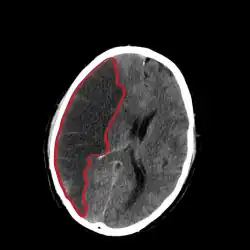

| CT scan slice of the brain showing a right-hemispheric cerebral infarct (left side of image). | |